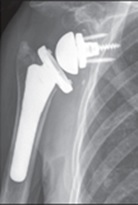

因應上述術後的問題,專家們轉而從肌腱移轉 (Tendon Transfer) 的概念,嚐試用 肩三角肌就近取材兼代旋轉肌袖的作用。1990年代,開始有了反轉式肩全人工關節置換術( Reverse Total Shoulder Arthroplasty) (圖6-1) 的創新手術,

![]() |

| 圖 6-1 反轉式肩全人工關節 |

反轉式全人工肩關節置換術,幾經多次修改,術後的臨床表現的確比傳統式肩全人工關節 (圖7)

好很多,術後關節的疼痛、 僵硬、 活動度都大有改善,術後併發症也大大減少。